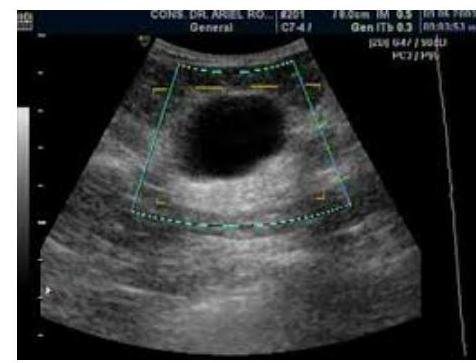

# PATOLOGÍA MAMARIA BENIGNA ## DEFINICIÓN Se entiende por patología benigna mamaria a un grupo de alteraciones en el tejido mamario las cuales no tienen la capacidad de diseminarse, que responden a mecanismos de tipo hormonal, factores externos como son los hábitos nutricionales y estilos de vida que interactúan entre si creando un grupo de signos y síntomas muy variados que se manifiestan por dolor mamario, masas, nodularidad, turgencia, irritabilidad, secreción y descarga por el pezón y/o inflamación e infección, que en algunos casos pueden elevar el riesgo de patología mamaria maligna. ## EPIDEMIOLOGÍA - Más de la mitad de todas las mujeres desarrollan alguna forma de enfermedad benigna después de los 20 años. - El Ca de Mama en México se encuentra en un 12% en edad reprocutiva (Mastografía con limitación). - Los tumores constituyen el 20% de la patología mamaria, los hay de contenido sólido y líquido. - El FIBROADENOMA MAMARIO es el tumor benigno más frecuente. Las condiciones más frecuentes son: - Mastalgia - Fibroadenoma (FAM) - Condición Fibroquísitica (CF) - Papiloma Intraductal - Mastitis. ## FACTORES DE RIESGO - BRCA1 y BRCA2 - Anticonceptivos Orales y Terapia de reepmplazo hormonal - Gestación y lactancia - Menstruación, perimenopausia y posmenopausia - Hiperestrogenismo - Tabaquismo - Dietas ricas en grasa. # DETECCIÓN - La edad recomendable para el inicio del examen médico mamario rutinario es a partir de los 19 años. - En pacientes con BRCA1 y BRCA2 deben iniciar la exploración médica mamaria entre los 18 a 21 años de edad. ## EXPLROACIÓN CLÍNICA MAMARIA 1. Realizar entre el 50 y 70 día posterior a la menstruación (en menopáusicas puede ser un día fijo). 2. Se inicia con la Inspección de la pacientes sentada, con las manos en la cadera y posteriormente brazos a la cabeza. 3. Se explora el tamaño de las mamas, su simetría, lesiones ulcerativas, hoyuelos, resequedad de piel, retracciones, masas visibles, o eritema, la palpación mamaria puede ser en posición supina explorando completamente y sistemáticamente la mama, en forma circular, vertical u horizontal. Incluyendo la expresión del pezón y la exploración de ganglios axilares ## TRASTORNOS FUNCIONALES ## TELORREA Es la secreción espontánea pero no fisiológica procedente del pezón. Se encuentran diferentes tipos de secreción según el aspecto macroscópico de la misma. - Secreción Grumosa: la secreción es pegajosa y de aspecto hemorrágico. Puede ocurrir a cualquier edad pero es más frecuente en mujeres menopáusicas o perimenopáusicas y en presencia de mastopatía fibroquística. - Secreción Purulenta: puede manifestarse en los distintos tipos de mastitis. - Secreción Acuosa: es poco frecuente y suele sugerir una lesión maligna, por lo que se aconsejan estudios para descartar este diagnóstico. - Secreciones Serosas, Serosanguinolentas y Hemorrágicas: son los tipos más frecuentes. Su causa principal, sobre todo en unilaterales, es el PAPILOMA INTRADUCTAL.El pico de incidencia es en torno a los 40 años, pero a partir de los 50, la lesión más frecuente es el carcinoma y está indicada la biopsia siempre que se palpe algún nódulo. - Secreción Lechosao Galactorrea: se caracteriza por ser bilateral y pluriporificial. Asociada o no a hiperprolactinemia. # TRASTORNOS INFLAMATORIOS ## MASTITIS Las mastitis puerperales agudas son la forma más habitual de aparición, aunque ha aumentado la frecuencia de mastitis agudas no asociadas con la lactancia. Gérmenes más frecuentes: - S. aureus - S. epidermidis - Estreptococos. La infección puede progresar y originar un absceso que requiere drenaje quirúrgico. El diagnóstico diferencial ha de establecerse con el carcinoma inflamatorio, que no suele acompañarse de fiebre, pero en caso de duda se realiza biopsia.  ## TRATAMIENTO 1. Manejo Sintomático 2. Dicloxacilina (en caso de alergia, Eritromicina) ## ENFERMEDAD DE MONDOR Que consiste en una tromboblebitis de las venas subcutáneas de la pared torácica secundaria a un trauma local. Puede persistir varios meses, pero no requiere tratamiento. ## MASTODINIA Consiste en un dolor mamario cíclico que AUMENTA EN EL PERIODO PREMENSTRUAL y se alivia tras la menstruación. La mastodinia es el principal síntoma de las Mastopatía Fibroquística. Debe distinguirse del dolor mamario en general (Mastalgia); siempre que exista dolor, se debe descartar la existencia de patología mamaria subyacente. # MASTOPATÍA FIBROQUÍSTICA/DISTLASIA MAMARIA ## DEFINICIÓN Se trata de una enfermedad benigna y crónica, caracterizada por una alteración en la proliferación del estroma y del parénquima mamario, desarrollando tumores o quistes palpables. - Es la patología más frecuente en la mujer premenopáusica y es muy rara después de la menopausia. Su etiología es desconocida, proponiéndose una influencia de un desequilibrio hormonal, con hiperestrogenismo, aunque no es constante. ## CLÍNICA No hay una clínica específica para la Mastopatía Fibroquística. ## DOLOR MAMARIO (el más frecuente) - Suele ser premenestrual y mejora con la menstruación (MASTODINIA) - El dolor es bilateral - Pueden aparecer induración o nódulos palpables. - Secreción de pezón. El embarazo y la lactancia ponen en reposo la MFQ. ## CLASIFICACIÓN Para determinar el riesgo de degeneración a cáncer de mama, se valora la existencia de proliferación del componente epitelial y si hay atipia o no en esa proliferación, distinguiéndose 3 tipos de MFQ. | NO PROLIFERATIVA | 68 % | | :-- | :--: | | PROLIFERATIVA SIN ATIPIA | 26 % | | PROLIFERATIVA CON ATIPIA | 4 % | | Lesiones No Proliferativas | - Fibroadenoma (Tumor más común) - Quistes - Hiperplasia Leve o Usual - Calcificaciones Epiteliales - Papila con Cambios Apocrinos | | :--: | :--: | | Lesiones Proliferativas Sin Atipia | - Adenosis Esclerosante - Lesiones Radiales y Esclerosantes Complejas - Hiperplasia Moderada y Florida Usual - Papilomas Intraductuales | | Lesiones Proliferativas Con Atipia | - Hiperplasia Lobular Atípica - Hiperplasia Ductal Atípica | La mayoría de los cambios que se producen en la displasia no se relacionan con un aumento en la incidencia de cáncer de mama. El riesgo de cáncer está moderadamente aumentado en los tipos proliferativos con atipia, que son la hiperplasia ductal atípica y la hiperplasia lobulillar atípica. # DIAGNÓSTICO ## Clínica + Ecografía (o Mastografía) + Estudio Microscópico (citología e histología) ## PUNCIÓN-ASPIRACIÓN - Indicado en mastopatía fibroquístico de predominio nodular-quístico - Ofrece garantía diagnóstica, puesto que cura el quiste tras evacuación del contenido. ## TRATAMIENTO 1. En general la mastopatía fibroquística no requiere tx. 2. Se debe explicar a la paciente la benignidad del proceso y tranquiliza. 3. Tx médico - Progestágenos en la 29 fase del ciclo para compensar el hiperestronismo. 4. Pueden ser útiles progestágenos en gel para tx local y aceite de onagra. # FIBROADENOMA ## DEFINICIÓN Son masas circunscritas nítidamente, móviles y usualmente solitarias que ocurren comúnmente antes de los 30 años, aumentan su tamaño con el embarazo y suelen presentar regresión y calcificación posmenopáusicas. Es el tumor benigno más frecuente de la mama, formado por la proliferación de elementos epiteliales y mesenquimatosos bien diferenciados, predominando su carácter fibroso frente al glandular. Es pseudoencapsulado, bien delimitado del tejido mamario adyacente, móvil, esférico u ovoide, aunque puede ser multilobulado. ## EPIDEMIOLOGÍA - Se observa frecuentemente entre 20-40 años - Puede aparecer durante el embrazo - En menores de 35 años las masas mamarias son usualmente un Fibroadenoma. ## DIAGNOSTICO Clínica del nódulo de características benignas ## 1ra elección: ULTRASONIDO - Al tratarse de padecimiento en mujeres jóvenes será la técnica de elección para confirmar. - Patrón típico con nódulo sólido, regular, de bordes bien delimitados, ovoide, hipoecoico. - Calcificaciones grandes, gruesas, que aumentan con el tiempo. ## MASTOGRAFÍA - Tiene un papel limitado debido a que en las mujeres jóvenes la mama es radiológicamente muy densa, dificultando la valoración de las imágenes. - La imagen típica en mastografía es "palomitas de maíz". ## RIESGO DE CÁNCER - Aumenta si el Fibroadenoma es complejo - La mayoría no hay aumento en riesgo  - Lesiones bien definidas - Si se encuentran datos de MICROCALCIFICACIONES - Tomar biopsia. # TRATAMIENTO ## 1ra elección: Seguimiento clínico y por USG ANUAL ## Extirpación Quirúrgica: - Tamaño superior a 2 cm - Rápido crecimiento - Duda diagnóstica - Cancerofobia ## ADENOMA - Es un tumor bien delimitado, compuesto de elementos epiteliales diferenciados con escaso estroma. - No es frecuente y afecta sobre todo a mujeres jóvenes. ## TRATAMIENTO 1ra elección: Extirpación completa de la lesión. # PAPILOMA INTRADUCTUAL Se trata de proliferaciones exofíticas de células epiteliales de los conductos galactóforos sobre un eje fibrovascular. | PAPILOMA SOLITARIO | PAPILOMATOSIS MÚLTIPLE | | :--: | :--: | | Afecta a los conductos principales, localizándose a 1-2 cm del pezón. - Suele aparecer en mujeres premenopáusicas. - Es la causa más frecuente de telorrea. - No se asocia a riesgo de cáncer de mama CLÍNICA Telorrea sanguinolenta uriorificial espontánea, sin tumor palpable. TRATAMIENTO Extirpación quirúrgica del conducto que produce la telorragia. Suele recidivar. | Afecta a varios conductos y se origina en las unidades lobulillares terminales. - Se asocia a hiperplasia epitelial atípica. - Aparece en mujeres más jóvenes que el papiloma solitario. CLÍNICA No es tan habitual la presencia de telorrea. TRATAMIENTO Exéresis quirúrgica de una zona amplia alrededor de la lesión. 40%de los casos se asocian a Cáncer de Mama |  # GUESTE MAMARIO - Se suelen presentar en el contexto de la mastografía fibroquística y son MUY frecuentes. - La máxima incidencia se da entre los 40 - 50 años. GALACTOSELES: son una variante en donde los quistes de leche en mamas lactantes que cesan su actividad. ## CLÍNICA - TUMORACIONES INDOLORAS. - Se palpan de forma redondeada, lisa, móvil, no adherida, sensible y a la presión se nota tensión e incluso fluctuación. ## DIAGNÓSTICO ## 1ra elección: USG - Se visualizan nódulos anecogénicos de limites muy precisos. - Morfología regular y refuerzo posterior. ## TRATAMIENTO  ## ASPIRACIÓN POR PUNCIÓN Si un quiste mamario es palpable y visible, debe ser aspirado por punción. - Si su aspiración arroja líquido claro, transparente y sin sangre, no es necesaria la citología del líquido. - Requiere cita en 6 semanas para seguimiento. Si el quiste es un hallazgo únicamente por USG, no es necesaria su punción. ## PROCEDIMIENTO QUIRÚRGICO Si un quiste se resuelve posterior a la aspiración con un conteo por USG, no requiere mayor tratamiento. Si el quiste no desaparece posterior a la aspiración o existe recurrencia dentro de 6 semanas, se realiza una REMOCIÓN QUIRÚRGICA DEL QUISTE. # ECTASIA DUCTAL Aparece en mujeres perimenopáusicas y menopáusicas, más frecuentemente en fumadoras. Se presenta por dilatación de los ductos subareolares principales Da lugar a una secreción por el pezón, que si se infecta, puede abscesificar y fistulizar a piel. ## TRATAMIENTO - Extirpación quirúrgica. ## TUMOR PHYLLODES - Aparece en la 4 - 5 década de la vida. - Crecimiento rápido - Riesgo aumentado Sx Li-Fraumeni - Comportamiento Limítrofe benigno y maligno.  Figura 2: TF borderline recalcicado. ## TRATAMIENTO - Cirugía local RESECCIÓN AMPLIA margen mínimo 1 cm . - Pronóstico adverso puede ser tx paliativo.